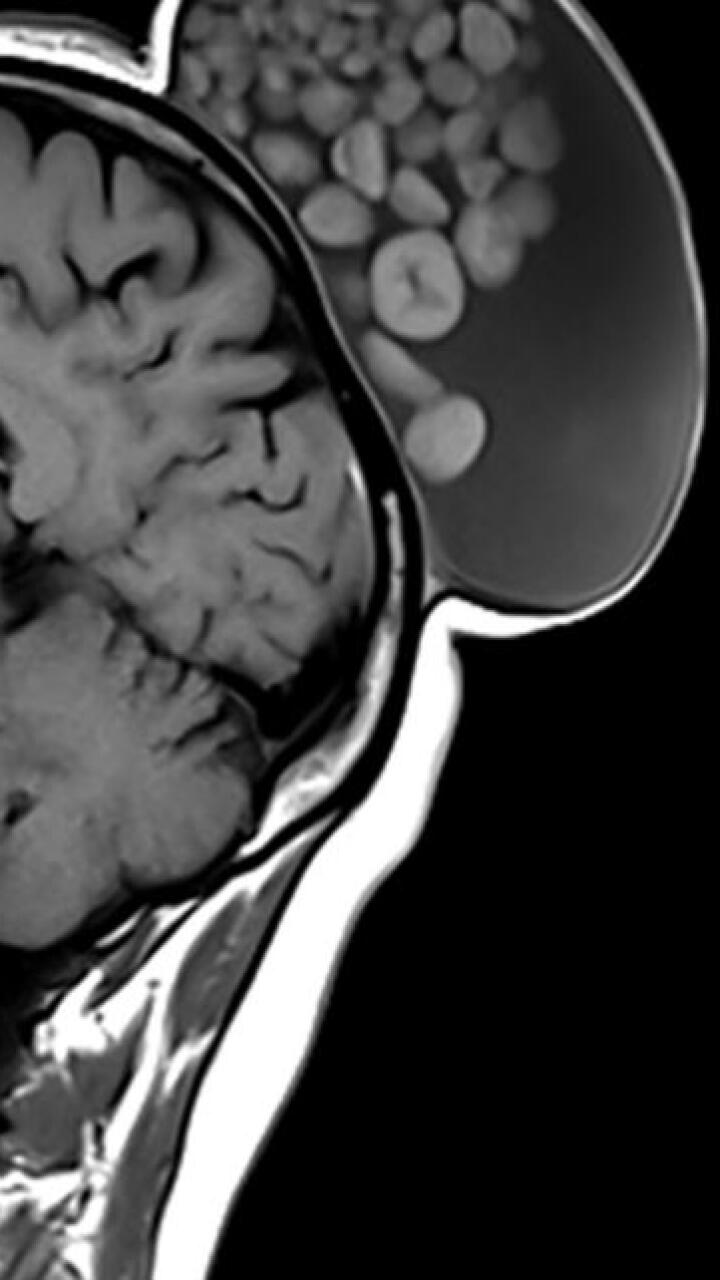

Luego de un examen, se percataron que la masa, que se ubicó en la región parieto-occipital, medía 15 cm de largo, 10 de ancho y 12 de alto.

Cuando eliminaron el crecimiento, notaron que la lesión estaba llena de moléculas de grasa, bolas de queratina, líquido y cabello.

Lo describieron como un “saco de canicas”

Las bolas encontradas se conocen como quistes dermoides, los cuales parecen tumores, pero, generalmente, no son dañinos, según explicó la Clínica Cleveland, citado por el medio New York Post.

Este tipo de quistes pueden contener hueso, líquido, cabello, nervios, piel, dientes o glándulas sudoríparas.